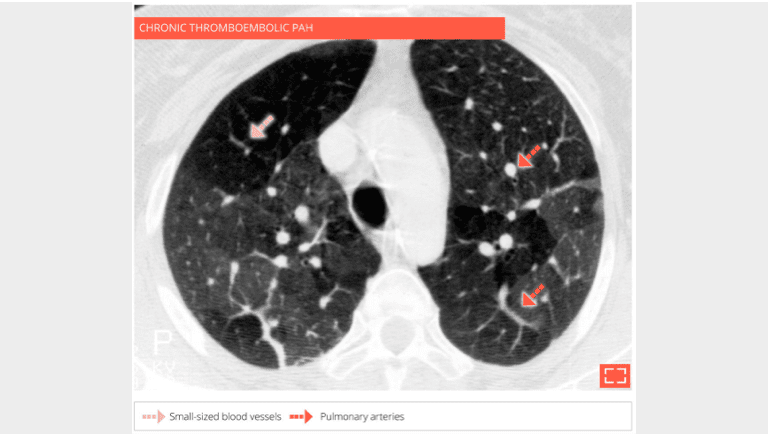

The hypodense regions of the lung contain smaller vessels, the number of which decrease while the size of the pulmonary arteries in dense regions increases corresponding to a redistribution of vascular flow to these perfused regions. A CT scan with injection of contrast agent synchronized to opacification of the pulmonary arteries, must confirm chronic thrombosis of the pulmonary arteries.

2. Vascular mosaic attenuation

Vascular mosaic attenuation

The CT scan with contrast medium injection to check for pulmonary artery obstruction shows the small size and distal thrombosis of peripheral pulmonary arteries, confirming chronic thrombosis. Ventilation-perfusion scintigraphy is the recommended exam for screening for these anomalies.